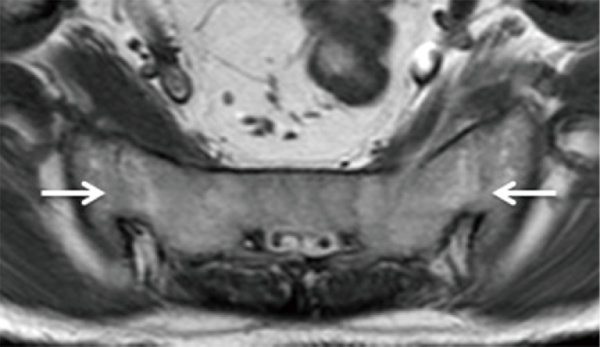

Kết quả chụp cộng hưởng từ cho thấy mức độ tổn thương của khớp cùng chậu, cơ, dây chằng, vết nứt gãy nhỏ tại khớp. Với phương pháp này, bác sĩ có thể chẩn đoán mức độ viêm của khớp cùng chậu từ giai đoạn khởi phát mà chụp X Quang và CT không phát hiện được.